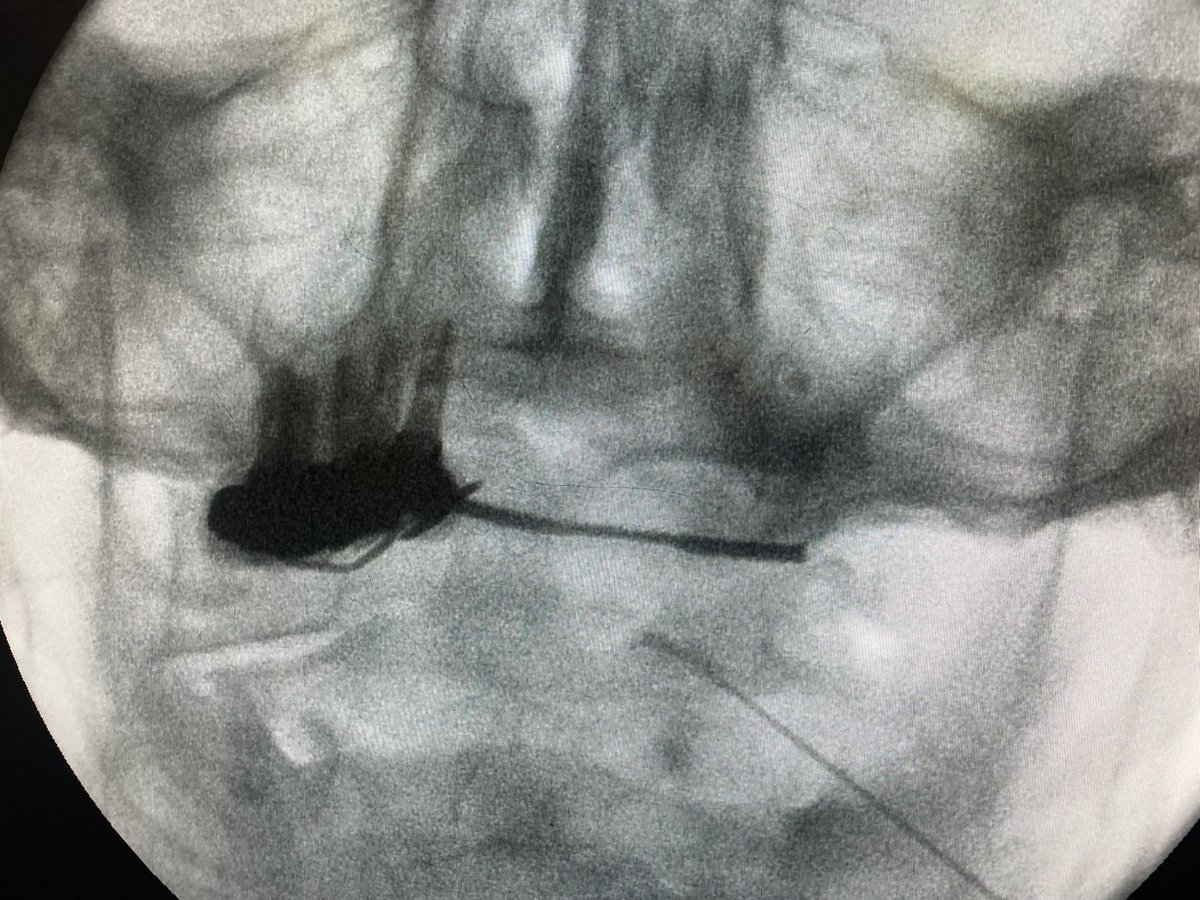

SDRC de rodilla. La importancia de una buena elección terapeutica hace que el alivio del dolor sea una realidad. Ayer implántanos elecyrodos de GRD en Pontevedra los Dres. Daniel Torres y Cristina Barreiro. Los servicios de anestesia: la piedra angular del tratamiento del dolor